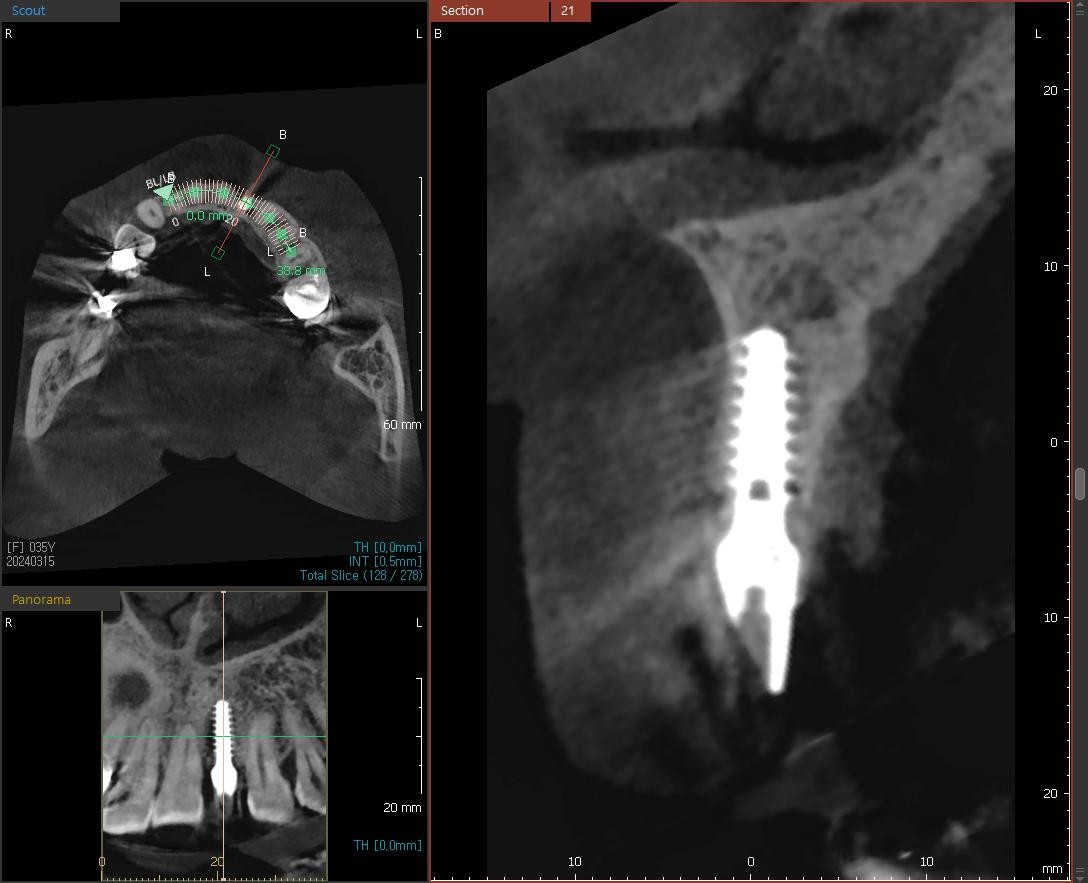

24³â 03 15ÀÏ ÀüÄ¡ºÎ½Ä¸³°í°ú °¡ÀÇÄ¡¸¦ ¸¸µé¾îÁÖ¾úÀ¾´Ï´Ù.

36¼¼¿© ȯÀÚºÐÀÔ´Ï´Ù.1¿ù¿¡ ¸¹ÀÌ Èçµé¸®°í »ÀÀÇ Èí¼ö°¡ ½ÉÇØ °ñÀ̽ĸ¸ ÇØ ³õ°í ÀÕ¸ö°ú °ñÁ¶Á÷À̾î´ÀÁ¤µµ Çü¼ºµÇ¾î ÀÓÇÁ¶õÆ®¸¦ ½Ä¸³ÇÏ¿´À¾´Ï´Ù.